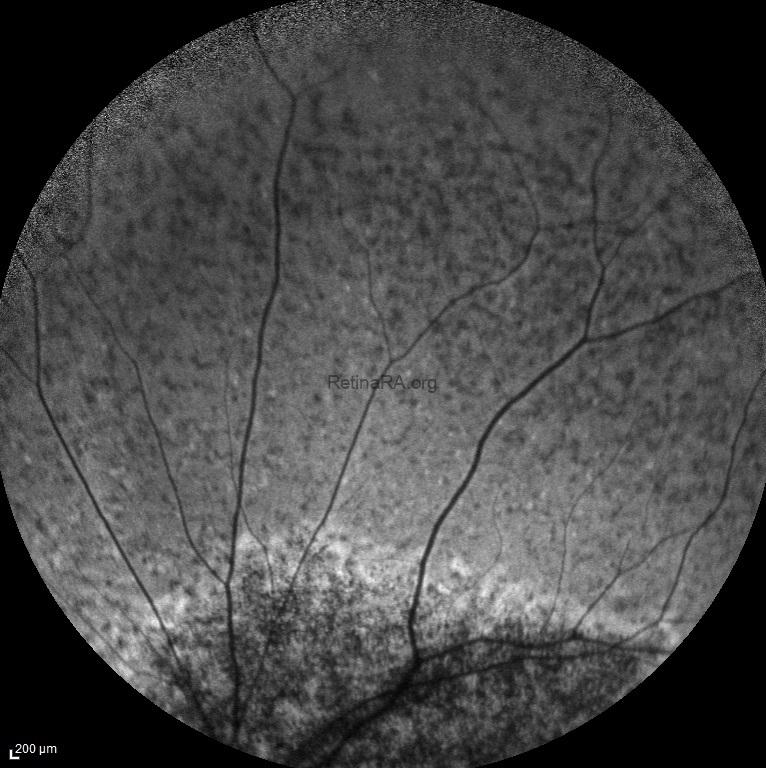

Infra-red reflectance images did not provide any specific features of disease.

Infra-red reflectance image of severe ABCA-4 retinopathy